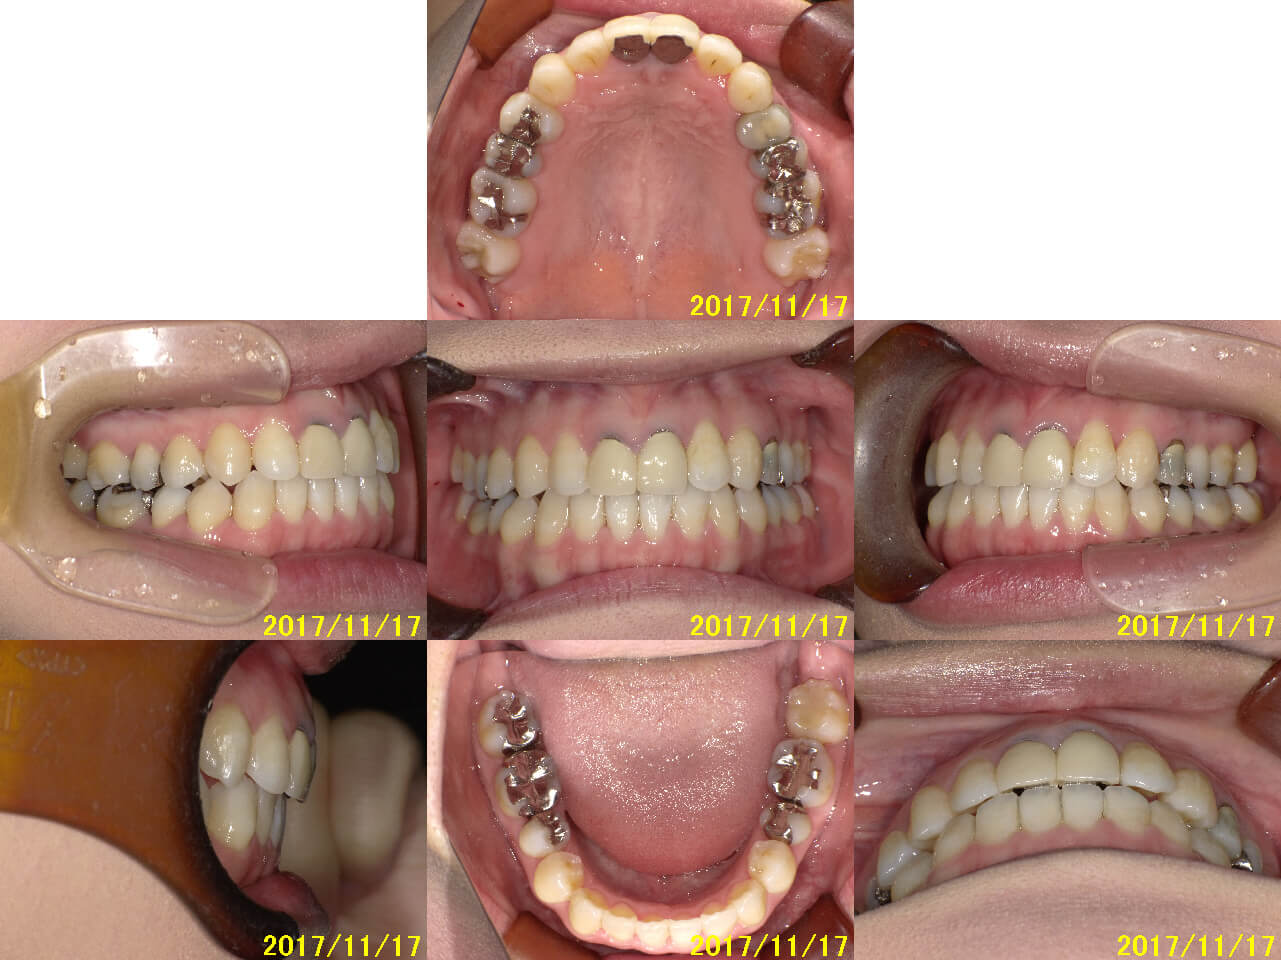

前回撮影したものと比較したいと思います!

(上:2017/10/6 下:2017/11/17)

今回はアタッチメントを除去した後に写真を撮ったので、歯が白く見えますね\(^o^)/(笑)

前回の全体写真から約1ヵ月の期間ですが、だいぶ変わっているのが写真でわかります☆

奥歯がしっかりと噛んで、隙間が減っています!